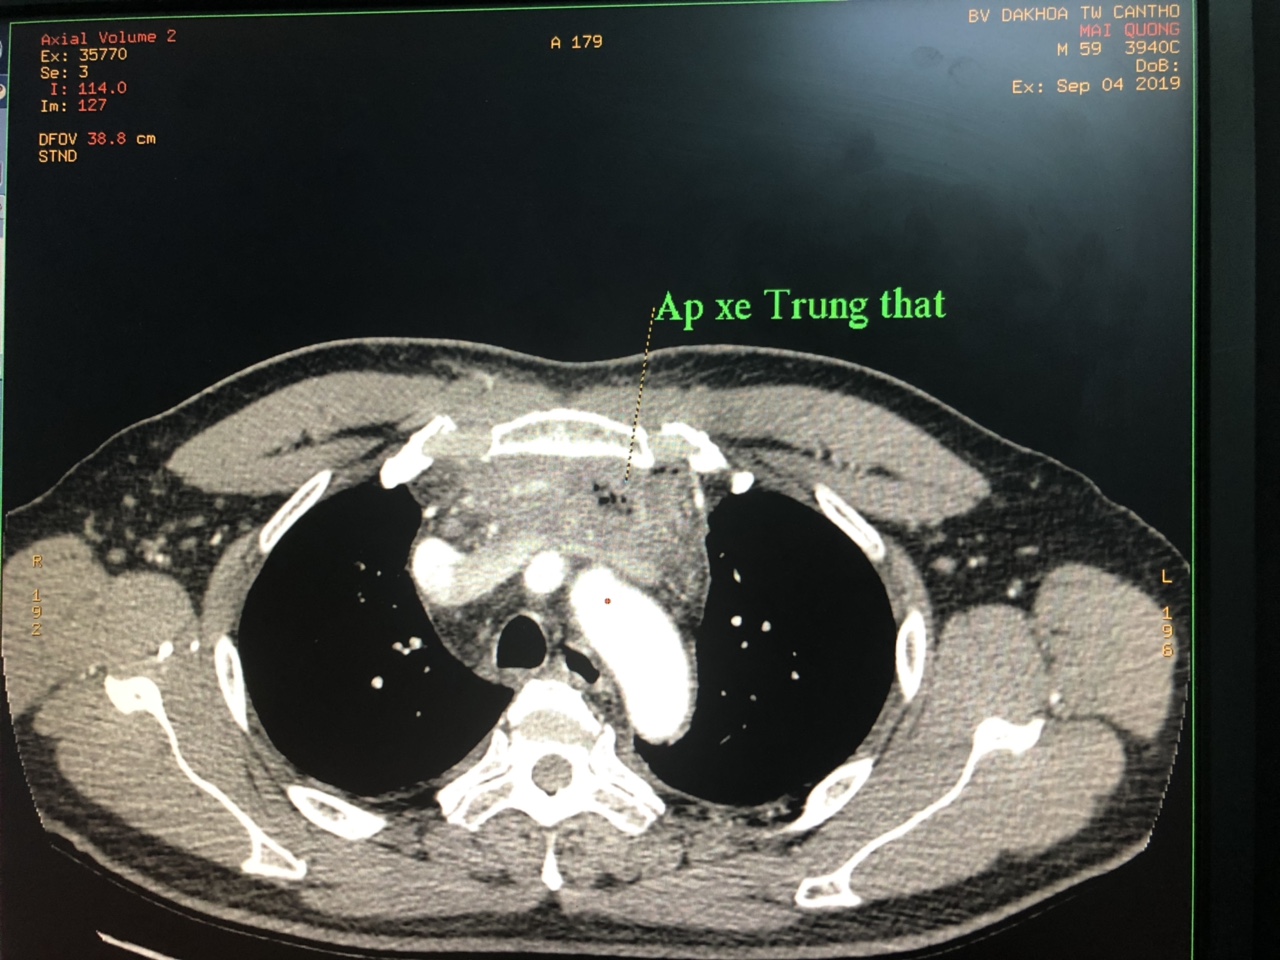

Bệnh nhân Mai Qương sinh năm 1960, Sóc Trăng. 1 tuần trước nhập viện bệnh nhân sưng đau vùng cổ 2 bên, lan xuống ngực nhập viện điều trị tại bệnh viện tỉnh 5 ngày, sau đó chuyển đến Bệnh viện đa khoa Trung ương Cần Thơ với chẩn đoán áp xe cổ - áp xe trung thất.

Tình trạng lúc nhập viện biểu hiện suy hô hấp, nhiễm trùng nhiễm độc, cổ bạnh do tràn khí dưới da. Kết quả C.T Scaner ngực có cản quang cho thấy: Tổn thương tụ dịch, khí vùng cổ đi từ xương móng, lan đến thất trước, khả năng áp xe vùng cổ; tràn dịch màng tim; tổn thương phế nang kèm xơ hóa đỉnh phổi phải, khả năng viêm; tràn dịch màng phổi hai bên.

Kết quả siêu âm tràn dịch màng phổi 2 bên lượng ít. Chẩn đoán: áp xe cổ lan xuống trung thất, tràn dịch màng tim tiên lượng rất nặng.